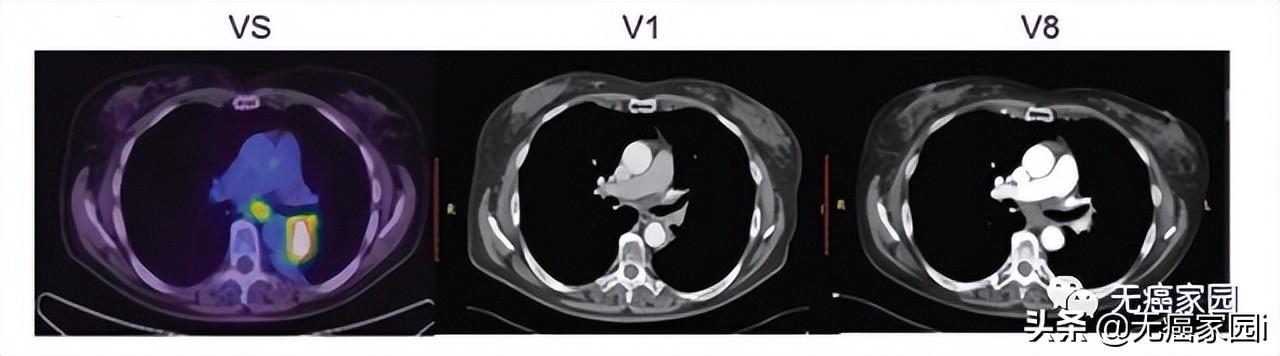

本研究中,采用局部输注 NKG2Dp CAR-NK的方式治疗了3 例转移性结直肠癌患者。前两例患者腹腔输注低剂量 CAR-NK 细胞后,可观察看 腹水生成量减慢以及腹水样本中肿瘤细胞的数量急剧减少 。 第三例肝转移瘤患者 采用超声引导下瘤内经皮注射和腹腔内灌注方式输注 CAR-NK细胞后, 多普勒超声可见肝部肿瘤快速缩小 ,正电子发射断层扫描 (PET-CT)提示经治疗的肝病灶为完全代谢反应。 3 例患者在治疗过程中均无出现3级或以上的不良事件。

第3例患者多普勒超声成像显示局部注射 CAR-NK 细胞降低肝转移病灶肿瘤负荷

CAR-NK 细胞治疗后肝转移病灶 PEC-CT 结果对比图

(患者肝Ⅵ段的最大氟脱氧葡萄糖(FDG)摄取值从 8.2 降至 0.14,经评估为完全代谢缓解)